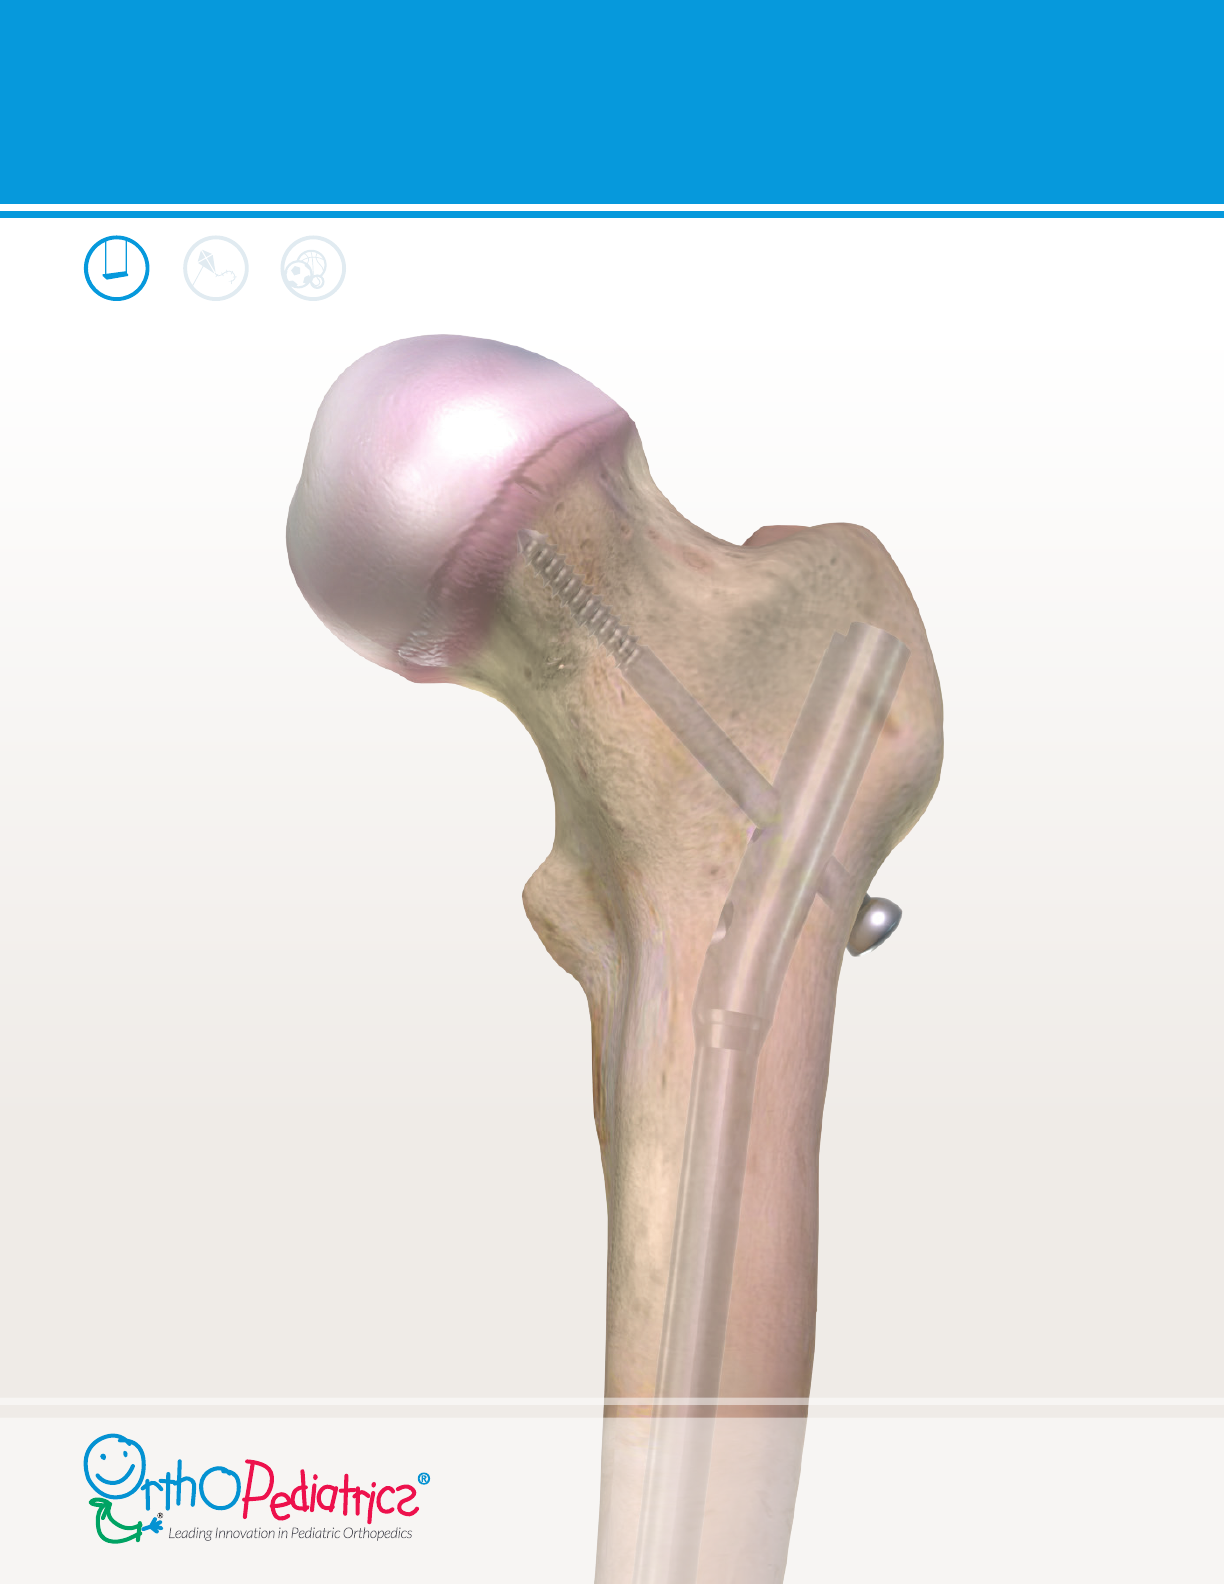

PediNail™ Pediatric Femoral Nail

SURGICAL TECHNIQUE